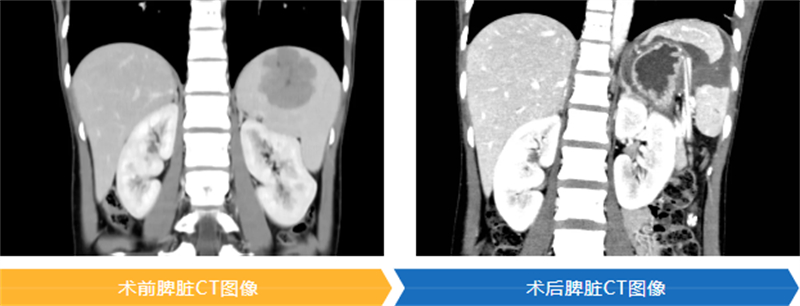

術前,中心肝膽胰外科團隊制定了周密的手術方案,充分評估手術關鍵和風險,聯合醫學影像科3D重建技術,模擬手術過程,精準評估腫瘤供血血管,確定需要結扎的脾段血管及需切除脾段,評價預保留脾臟的供血血管。手術當天,手術團隊在高清腹腔鏡放大視野下,運用超聲刀及止血系統實現對脾臟腫瘤的精準解剖性切除,從而實現微創技術與保留脾臟功能的平衡,手術耗時2小時20分鐘,術中出血量僅為50ml。術后病理檢查結果回報為脾臟血管瘤。

在快速康復外科理念的指導下,術后第1天,龐女士即恢復半流質飲食及下床活動,出院前復查CT提示剩余脾臟血供正常,血小板也未見明顯升高,術后第5天順利出院。